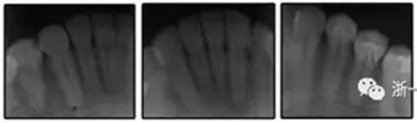

圖3. 治療前頭影側(cè)位片,頭影測量描跡圖和全口X光片

患者是一名39歲的白人婦女,病史不明。她主訴是她的右側(cè)顳下關(guān)節(jié)有不適癥狀,并希望改善她的笑容。她有一個對稱的臉型和一個II類2分類的微笑。她的側(cè)貌是凸的,90°的鼻唇角和骨性下頜骨發(fā)育不足??趦?nèi),上頜中線與面部重合,但下頜中線向右側(cè)偏移5mm;存在6mm的深覆蓋。她的兩側(cè)都是I類磨牙關(guān)系,左側(cè)是I類尖牙關(guān)系,右側(cè)是完全的II類尖牙關(guān)系。下頜右側(cè)第二前磨牙先天性缺失(圖1和圖2)。最初的全景片顯示了足夠的骨質(zhì)水平和全部的第三磨牙(圖3)。治療前的頭影測量片片和相應(yīng)的頭影測量圖(圖3)證實ANB為7°,Wits評估為6 mm的骨性II類錯合(表)。上頜切牙相對與面部和顱底的位置很好。下頜切牙前傾。診斷為II類2分類錯合畸形,伴有骨性下頜發(fā)育不足,右側(cè)顳下頜關(guān)節(jié)癥狀,下頜中線向右側(cè)偏移5mm,先天性右下第二前磨牙缺失。